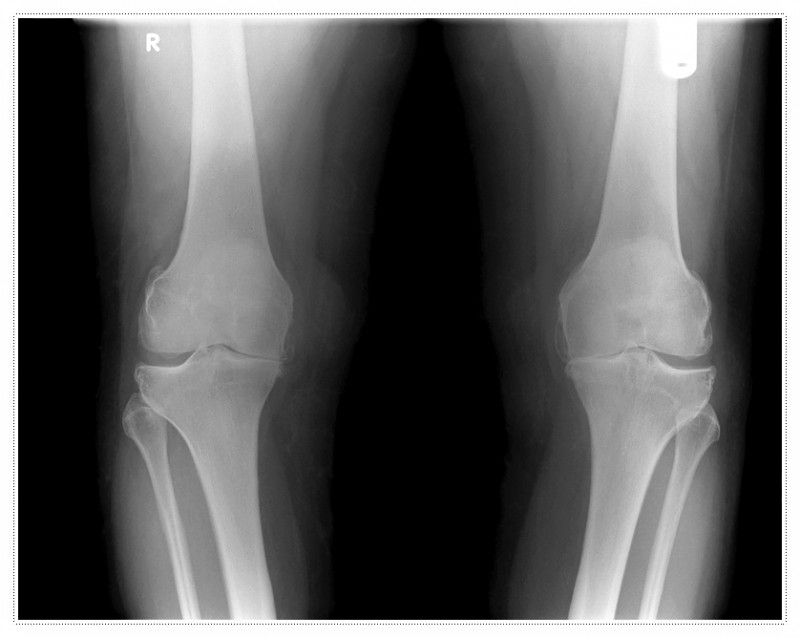

무릎 통증의 원인을 연골 손상 하나로만 생각하시는 분들도 많습니다.

물론 연골 상태는 매우 중요하게 살펴봐야 할 부분입니다.

하지만 저는 연골뿐 아니라, 무릎을 지탱하는 근육 사용 패턴이나 관절의 미세한 움직임 제한까지 함께 살펴보고 있습니다.

그 이유는 이러한 요소들이 실제 통증의 원인으로 작용하는 경우도 적지 않기 때문입니다.

특히 수술 후에는 무의식적으로 무릎을 보호하려는 움직임이 생기게 됩니다.

이 과정에서 특정 근육만 과도하게 사용되거나, 반대로 잘 쓰이지 않는 근육이 생기기도 하죠.

이런 상태가 지속되면 회복이 더뎌질 수 있고, 재발 위험 역시 높아질 수 있습니다.